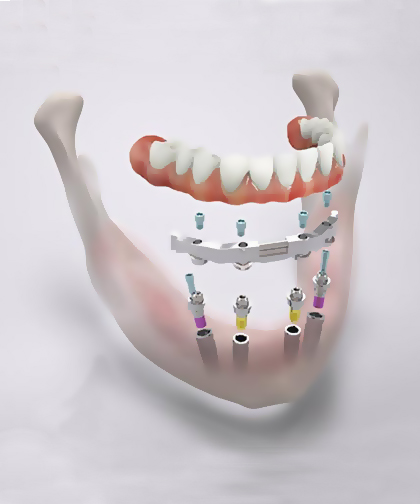

Протокол All-On-6 дозволяє встановити 6 імплантів, два з яких – у передній відділ щелепи, а чотири – у жувальний. Це зменшує потребу у кістковій пластиці, навіть при недостатності кісткової тканини, і дозволяє провести імплантацію за один прийом.

Ортопедичний етап

Лікар встановлює мульти-юніт абатмент на титанові імплантати. І лише тоді знімає зліпок та створює майбутню ортопедичну конструкцію.

Новий протез ставлять відразу або в день операції, або протягом 3-7 діб. Лікар складає рекомендації щодо догляду за тимчасовим протезом, розповідає про обмеження на період адаптації та визначає дату контрольного прийому. Протягом шести місяців імпланти повністю приживаються. Після цього можна встановити постійний протез.

У деяких випадках проведення імплантації за методом All-On-6 протипоказано, тому що не вистачає надійної опори. Тоді лікар вдається до протоколу All-on-6. Як правило, його використовують для пацієнтів із сильною атрофією кісткової тканини, гіпертонусом жувальних м'язів, пародонтитом та пародонтозом. Цей метод дозволяє встановити на штучне коріння протези з 14 коронками, а не з 12.